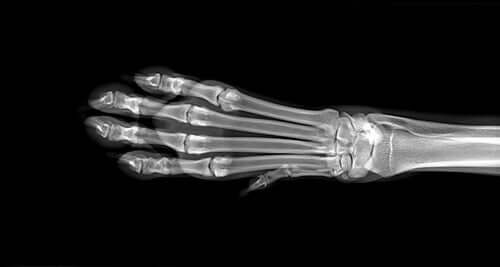

Aby ustalić przyczynę obrzęku, weterynarz wykona szereg badań diagnostycznych, w tym badania krwi i moczu, a także prześwietlenia kończyn. W przypadku, gdy te ostatnie nie są rozstrzygające, może być wymagany rezonans. Jeśli podejrzewa się kostniakomięsaka zostanie wykonana biopsja kości.